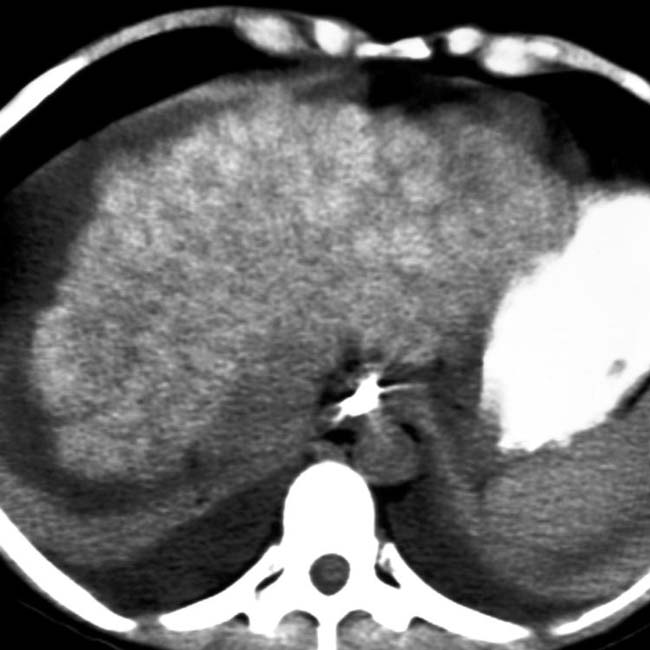

From radiologykey.com

Wilson Disease Radiology Key What Race Is Wilson S Disease Most Common In 3 in caucasians, the prevalence is 1 per 28,000 to 50,000 people. Hepatic wilson’s disease, which tends to develop earlier than neuropsychiatric wilson’s disease, ranges from mild liver disease to cirrhosis; Wilson disease occurs in all races and ethnic groups. In children, fatty liver is common. In studies conducted in asia, the prevalence ranges from 1 per. Wilson's disease is. What Race Is Wilson S Disease Most Common In.